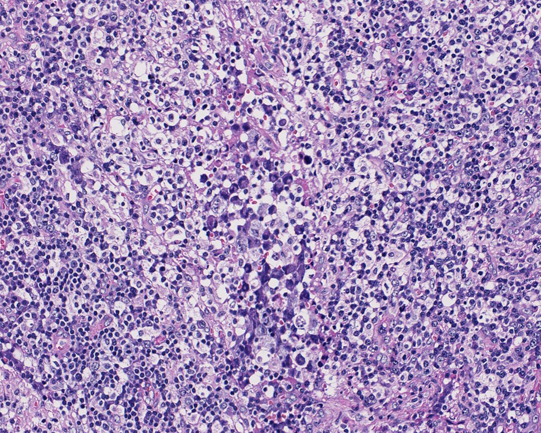

リンパ節組織所見

HE NZX10HE NZX40HE NZX40

大型異型細胞が集簇し結合性に増殖している。未分化癌や悪性黒色腫が鑑別となる。細胞は大型で類円形, 楕円形核に加えて腎臓様の特異な核形を示す。